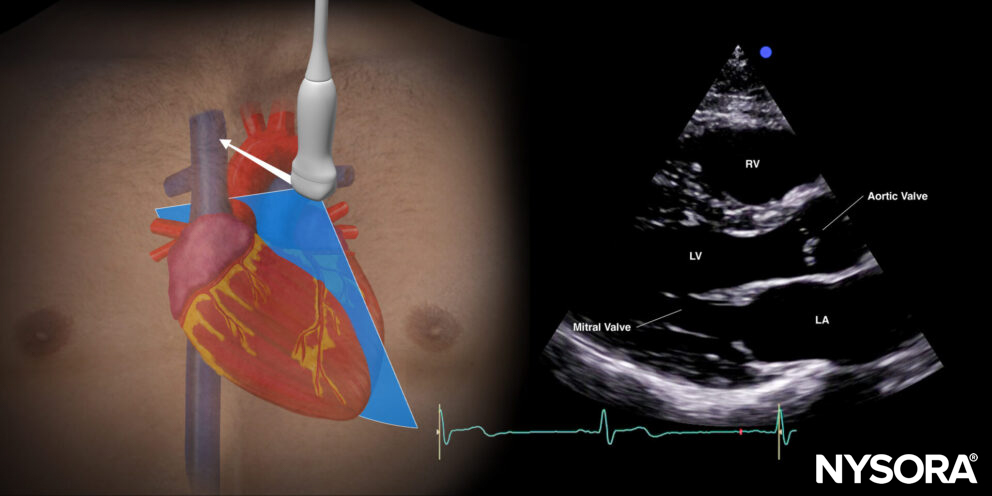

The standard parasternal long-axis view cuts the heart through the sagittal plane.

Sonoanatomy of the heart in the parasternal long-axis view. Left ventricle (LV), left atrium (LA), mitral valve, aortic valve, right ventricle (RV).

Reverse ultrasound anatomy

Reverse Ultrasound Anatomy of the heart in the parasternal short-axis view. Left ventricle (LV), left atrium (LA), mitral valve, aortic valve, right ventricle (RV).

Practical use:

- Left ventricle size and function

- Pericardial effusion

- Valve function: mitral valve prolapse, mitral valve regurgitation, aortic stenosis